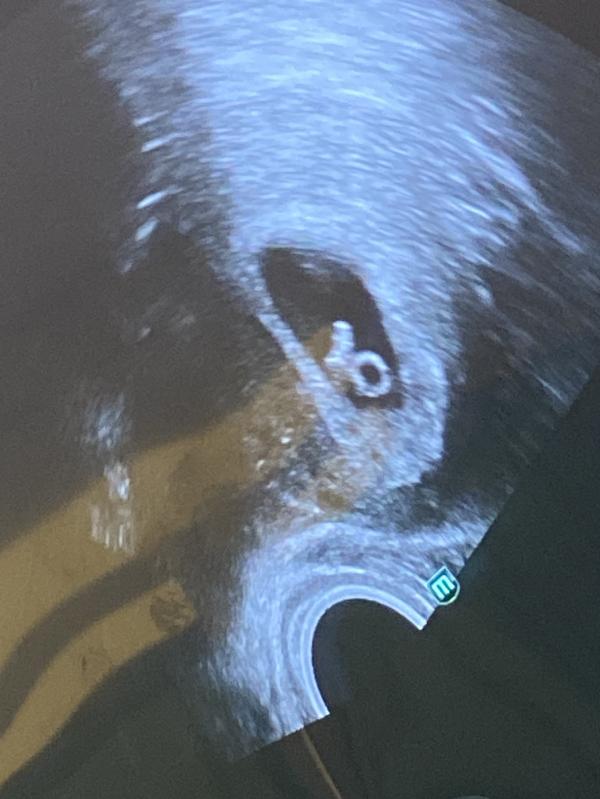

28 дней после переноса эмбриона: 6 недель беременности

28дпп , 6 недель 4 дня 🥰🫂

Да есть 127 ударов 😍